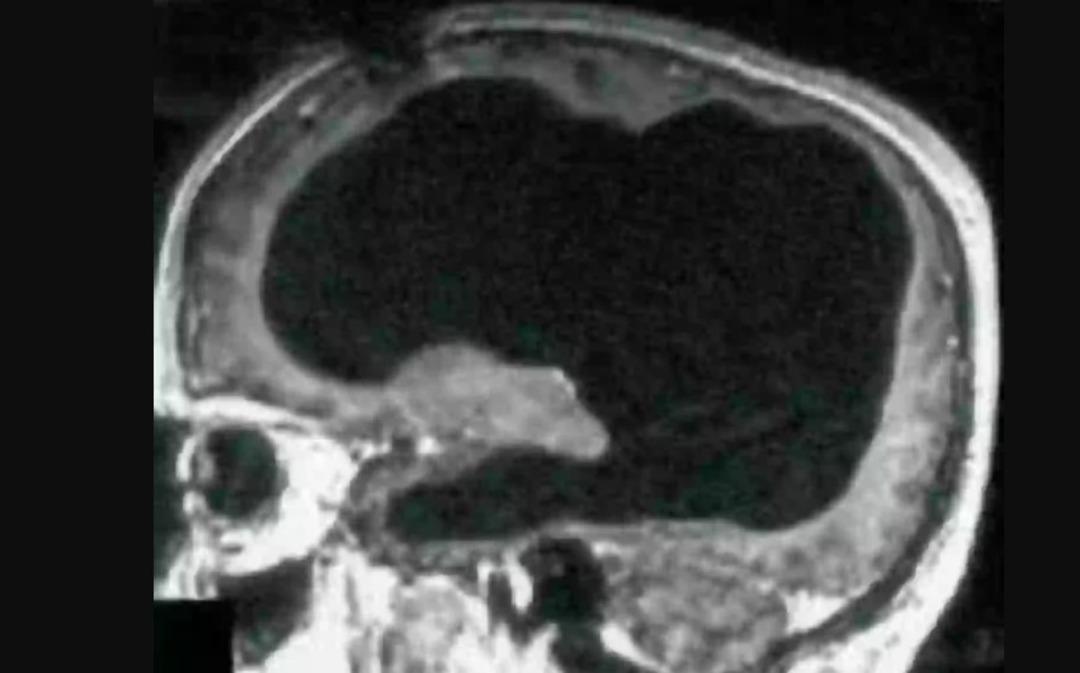

MYNET|DIŞ HABERLER Fransa'da yaşayan 44 yaşındaki ismi açıklanmayan bir hasta yaklaşık iki haftadır bacağında herkesi hissedebileceği gibi hafif bir ağrı ve güçsüzlük fark edince hastaneye gitti. Ağrı ve güçsüzlüğün ciddi bir şey olmadığından emin olmak için hastaneye gittiğini ifade eden hasta, "hidrosefali" olarak bilinen beyinde ve beyin çevresinde aşırı sıvı birikmesinden muzdaripti.

Bilişsel psikolog Axel Cleeremans vakaya ilişkin olarak yaptığı açıklamasında, "Normal bir hayat yaşıyordu. Bir ailesi vardı ve normal insanlar gibi çalışıyordu. Şikayeti sırasında IQ'su test edildi. Bu, normal aralığın biraz altında olan 84 çıktı. Beyin taraması yapılınca ise gerçek ortaya çıktı" dedi.

Doktorlar, hastalığından dolayı beyninde biriken sıvı nedeniyle beyninin büyük kısmının 30 yıl boyunca yavaş yavaş tahrip olduğuna inanıyor. Hastalığın teşhisi bebekken konulan Fransız hasta, bebekken kendisine stent takıldığını ancak 14 yaşındayken stent çıkarıltıldığını söyledi. Stentin çıkartılmasının ardından ise beyninin büyük bir kısmının aşınmış göründüğü ifade edildi.